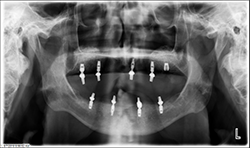

Fig.9

At a second appointment, four Bicon SHORT implants, three 4 x 6 mm and one 3.5 x 8 mm were placed in the mandibular arch (Figs. 9, 10). After normal healing time, both the maxillary and mandibular arches were fitted with a fixed hybrid prosthesis fabricated from a TRINIA substructure and Ceramage denture teeth. The patient was happy with the fit, function and comfort (Fig. 11).